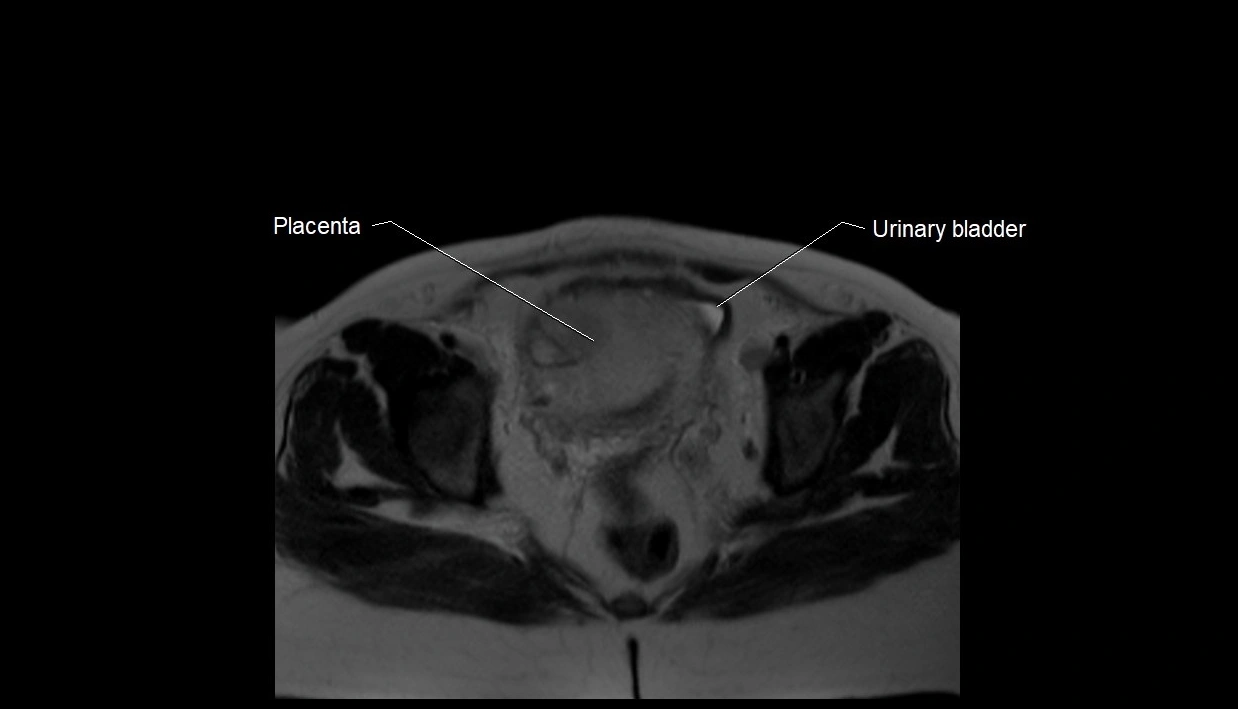

MRI Appearance

T2 HASTE (T2 GRE):

• Amniotic fluid shows very bright hyperintense signal

• Provides natural contrast against fetus and placenta

MRI image

image